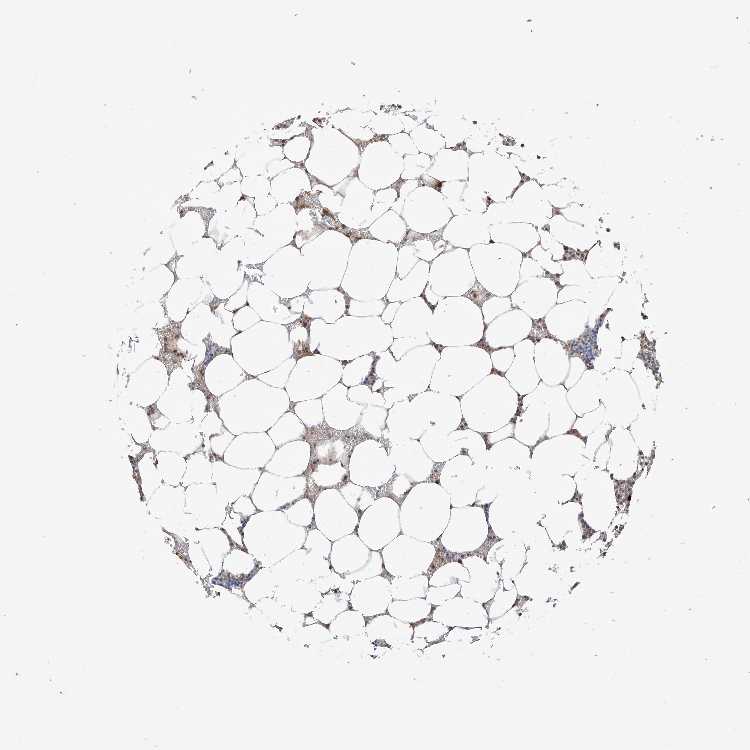

BONE MARROW - Antibody stainingi

Antibody staining in the annotated cell types in the current human tissue is reported as not detected, low, medium, or high, based on conventional immunohistochemistry profiling in selected tissues. This score is based on the combination of the staining intensity and fraction of stained cells.

Each image is clickable and will lead to virtual microscopy that enables deeper exploration of all samples and also displays staining intensity scores, fraction scores and subcellular localization as well as patient and tissue information for each sample.

Antibody HPA031804

Hematopoietic cells Medium